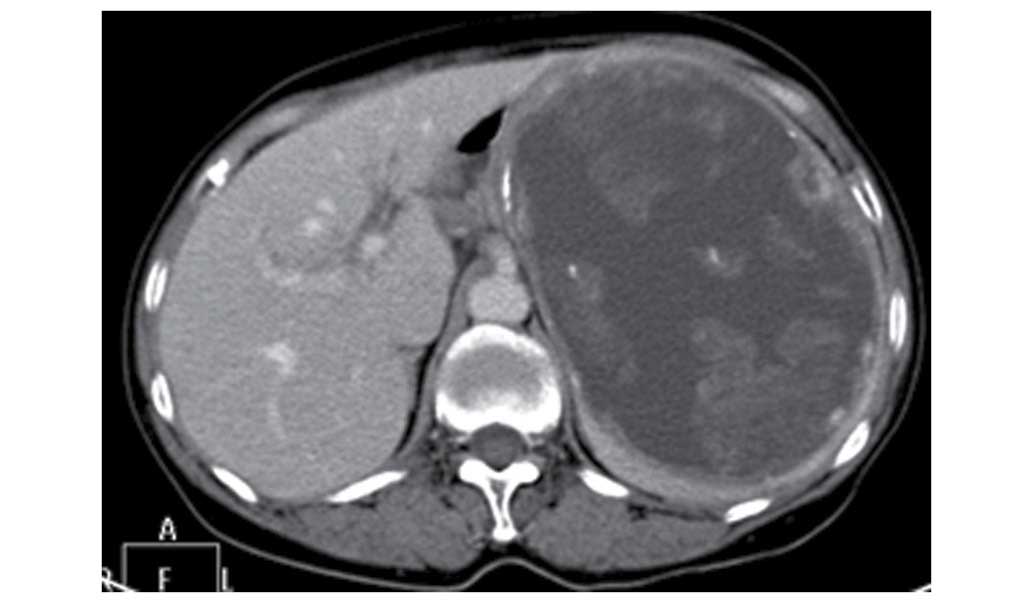

In July 2013, an abdominal mass was found in a 64-year-old woman (who did not present obvious symptoms at that time) at a health center in Suzhou, China. The patient was then hospitalized in the Affiliated Wujiang Hospital of Nantong University (Suzhou, Jiangsu, China) for further examination by computed tomography (CT). Non-enhanced CT showed that this mass measured 190×124 mm, and was located in the spleen where a massive shadow was visible. The lesion manifested as a lower hybrid density shadow and calcification, with clear borders (Fig. 1). Moderate inhomogenous enhancement was found at the arterial phase (Fig. 2) and inhomogenous continuous enhancement was found at the venous phase (Fig. 3) following gadolinium administration, and a delayed CT scan showed that the lesion was significantly enhanced (Fig. 4).

Figure 2.

Computed tomography scan showing moderate inhomogenous enhancement at the arterial phase following gadolinium administration.